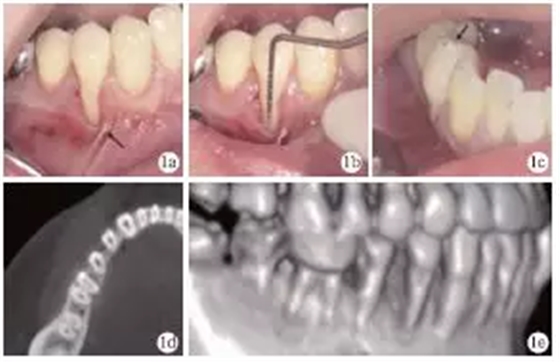

臨床檢查發(fā)現(xiàn),患者全口牙齦無明顯紅腫,探診深度1~4mm,BOP(+)<15%;#44頰側(cè)牙頸部充填物,頰側(cè)可見9mm齦退縮,超過膜齦聯(lián)合,僅存小于1mm的角化齦,且近中見系帶附著,近遠中齦乳頭均存在輕度退縮(圖1a、1b);正中咬合時可捫及#44功能性動度,頰尖舌斜面可見咬合高點(圖1c)。術(shù)前CT見#44頰側(cè)牙槽骨吸收達根尖1/3,鄰面擴展達根間區(qū),鄰面牙槽骨高度降低(圖1d、1e)。根據(jù)臨床檢查和CT檢查,診斷為#44Miller Ⅲ°牙齦退縮。

圖1 術(shù)前臨床及X線檢查